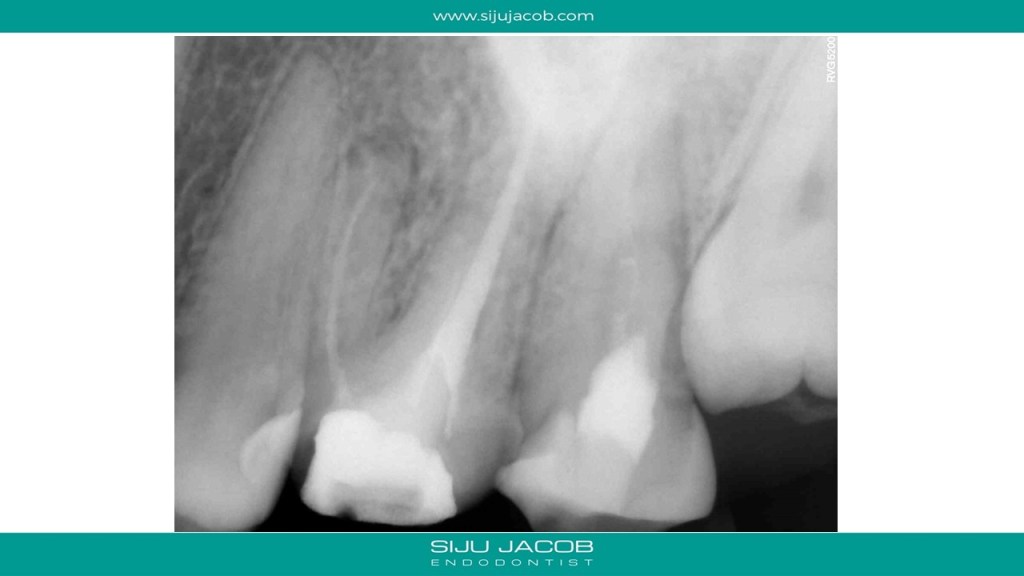

Some cases are such that when you eventually finish, you wonder what the fuss was all about. I struggled to locate the canals in this case. Not sure why. Yes, the access was difficult, but the main reason I struggled was probably the prior access that was made. This made me lose orientation initially. I managed to locate one canal and then took an Inter-appointment CBCT. This made things much easier. More in the short video below:

And below are the clinical slides of the same case: